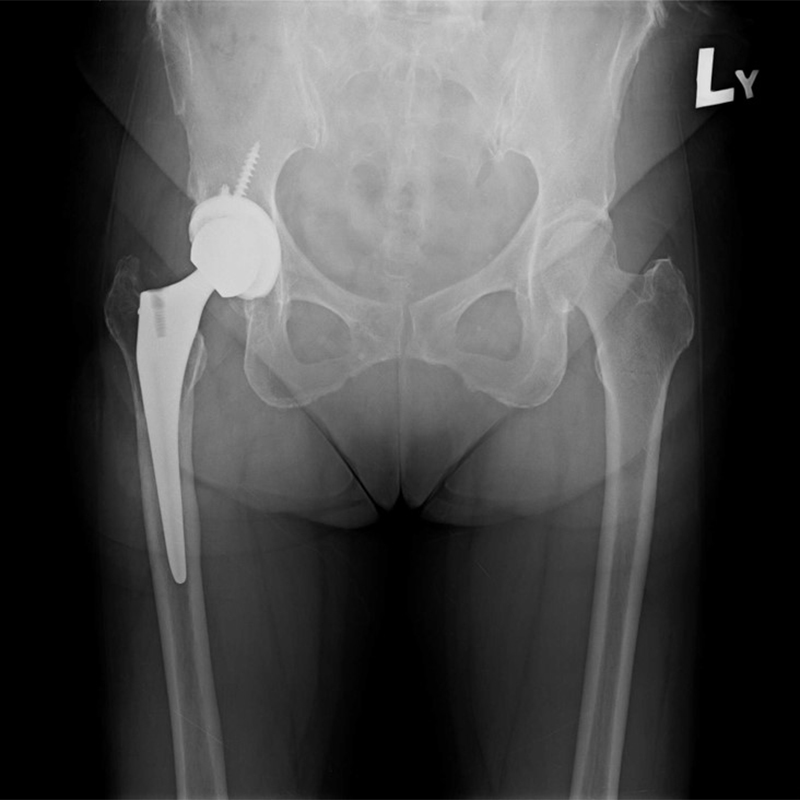

機器手臂手術 首頁 案例分享 髖關節手術 機器手臂手術 72歲 楊女士 退化性關節炎 術前 術後 60歲 彭先生骨股頭壞死 術前 術後 53歲 王女士退化性關節炎(DDH先天發育不全 CROWE TYPE 2) 術前 術後 83歲林女士退化性關節炎 術前 術後 83歲林女士退化性關節炎 術前 術後 楊女士 70歲 術前 術後 蔡女士 60歲 術前 術後